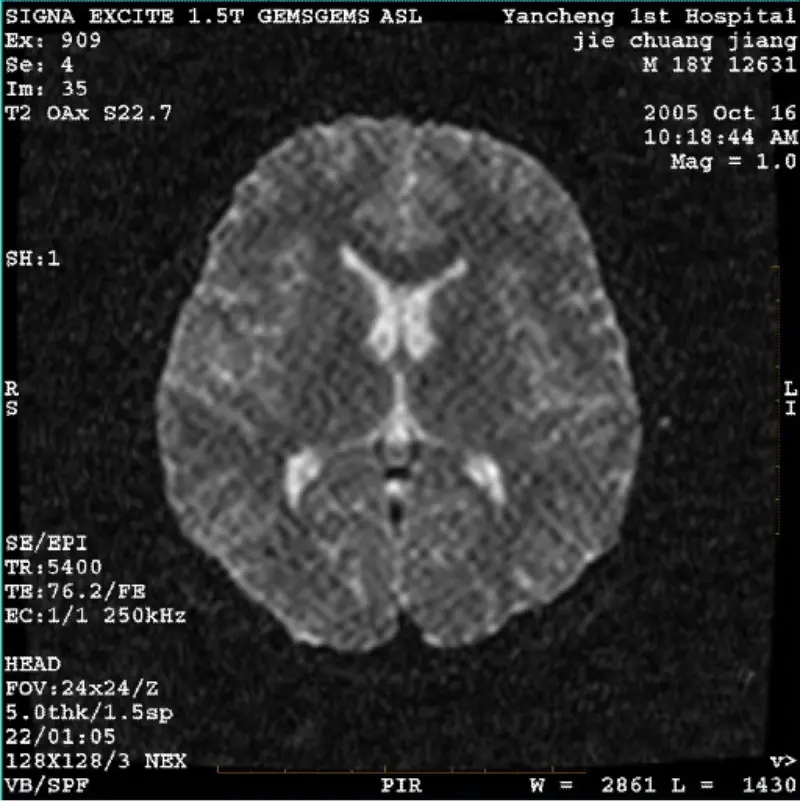

Lege plusSYSTEM: 1.5T Signa Twin Excite II (Software Version 11.0M4) PROBLEMA/SYMPTO DWI (Zoom modus et modus totus) et fiesta (zoom modus et modus totus) habens imaginem visibilis reticulata vel corduroy artificium utcumque cum usura corpus coil vel caput coil, alia translatio imaginis normali videtu......